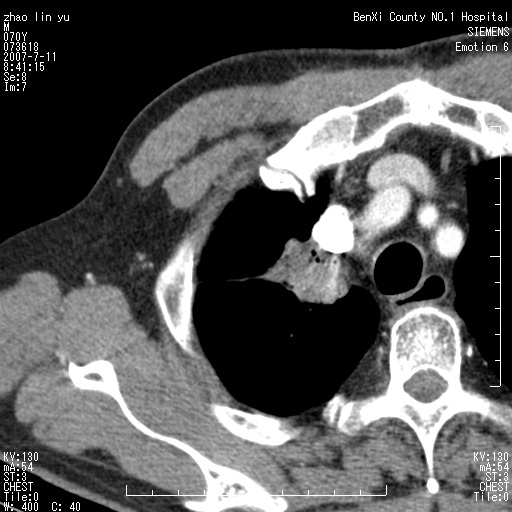

以下是引用王靖旗在2007-7-10 17:12:00的发言:[br] 男、70、咳嗽两个月,半年前换瓣手术,胸片未见异常,于昨天行x片发现右肺上野大片影,行ct扫描,这里是减薄图像,余肺正常。明天晚上会有增强扫描片,到时我会上传。[br][br] 冠状位请大家细看,应该是有意义的,[br][br] 请大家先看平扫发表意见。[br][br]

以下是引用zhangzhongshou在2007-7-10 21:43:00的发言:[br]右肺上叶周围型肺癌,以孤立型细支气管肺泡癌可能性大。